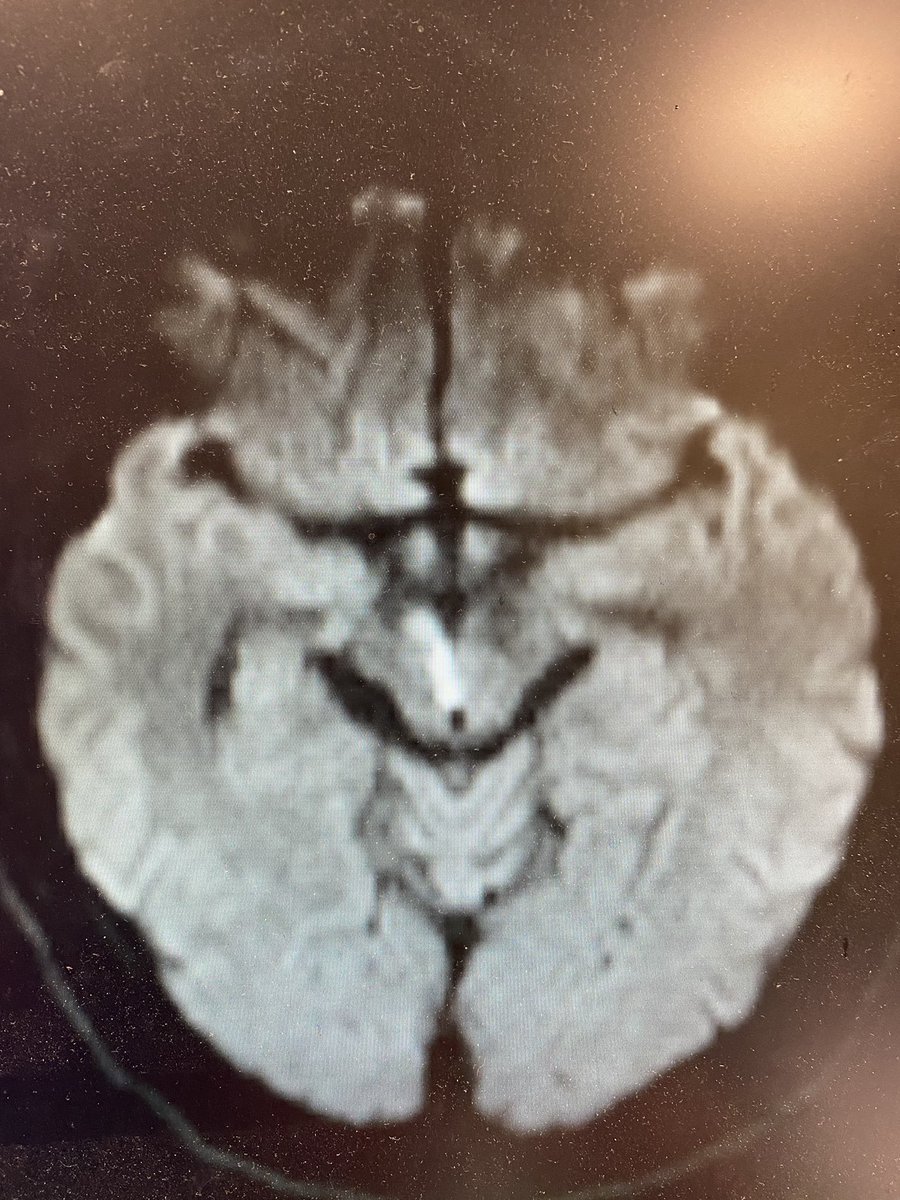

You got it! Artery of Percheron stroke leading to depressed mental status and nuclear IIIrd nerve palsy! Here is a first reference bmcneurol.biomedcentral.com 8/x

AOP infarcts affect bilateral para median thalamus and may also affect the midbrain and/or anterior thalamus. Presentation often involves depressed mental status, EOM deficits, aphasia, dysarthria, amnesia, ataxia, dystonia, weakness and sensory changes 10/x